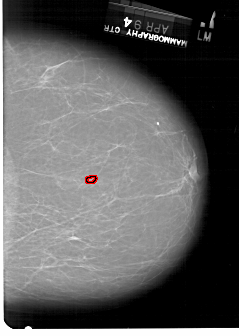

FILE: A_1331_1.RIGHT_MLO.OVERLAY

TOTAL_ABNORMALITIES 1

ABNORMALITY 1

LESION_TYPE CALCIFICATION TYPE PLEOMORPHIC DISTRIBUTION CLUSTERED

ASSESSMENT 4

SUBTLETY 1

PATHOLOGY BENIGN

TOTAL_OUTLINES 1

BOUNDARY